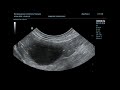

✅ Как проводится диагностика?